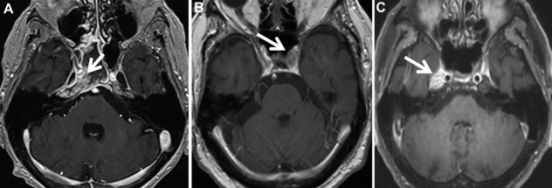

34.海绵窦和Meckel腔区不确定病变活检的诊断和预后:基于85例患者的回顾性病例分析

Diagnosis and Outcome of Biopsies of Indeterminate Lesions of the Cavernous Sinus and Meckel's Cave: A Retrospective Case Series in 85 Patients.

PMID: 29040711 DOI: 10.1093/neuros/nyx501

当海绵窦和Meckel腔区病变不能通过患者临床表现、实验室检查及影像学来确诊时,有必要进行活检确诊。作者对其所在机构收治的海绵窦和Meckel腔区无法确诊病灶的活检病例进行了分析研究,汇报如下:

研究中共纳入85例患者,其中22例有肿瘤病史。手术入路包括额颞入路(48例),内镜下经鼻入路(20例),经皮卵圆孔入路(12例)乙状窦后入路(5例)。最后确诊为转移瘤27例,颅内原发性肿瘤21例,炎症反应13例,出血11例,真菌感染5例,无法确诊或诊断的患者8例。13例有肿瘤病史的患者诊断结果与其先前的肿瘤诊断一致。2例患者因手术并发症死亡。

由上面的结果可知,在这些患者中,转移瘤最常见。因而,对于海绵窦和Meckel腔区病变的患者(尤其是有肿瘤病史者),如果临床或影像学诊断不确定,选择活检有更大的可能性诊断出转移瘤。尽管如此,作者认为活检应作为最后考虑的手段,因为活检可能会引起严重的并发症甚至死亡。

![]()